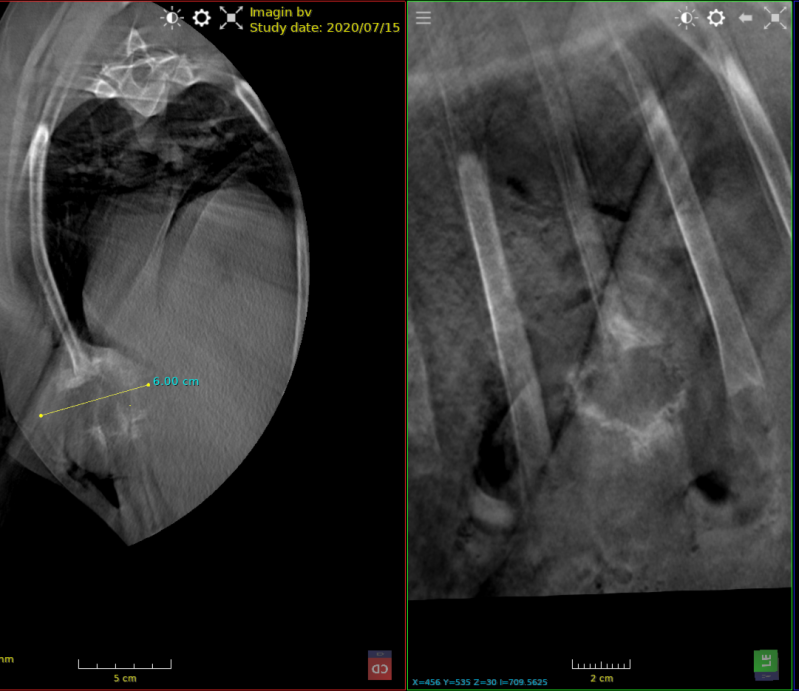

windhond met fractuur en luxatie os tarsale centrale